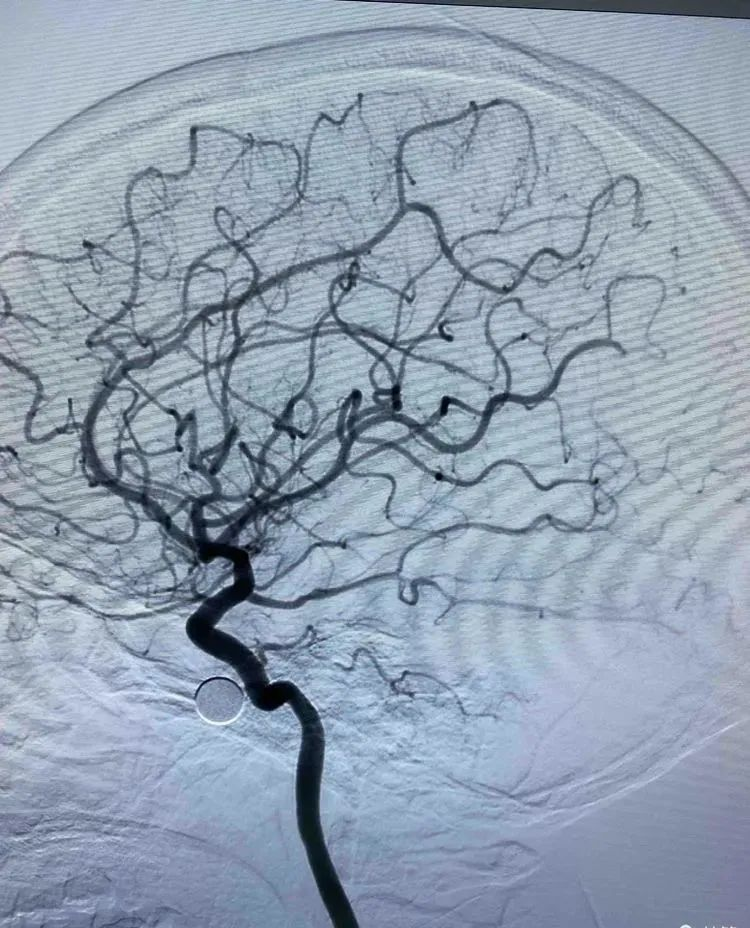

治疗过程